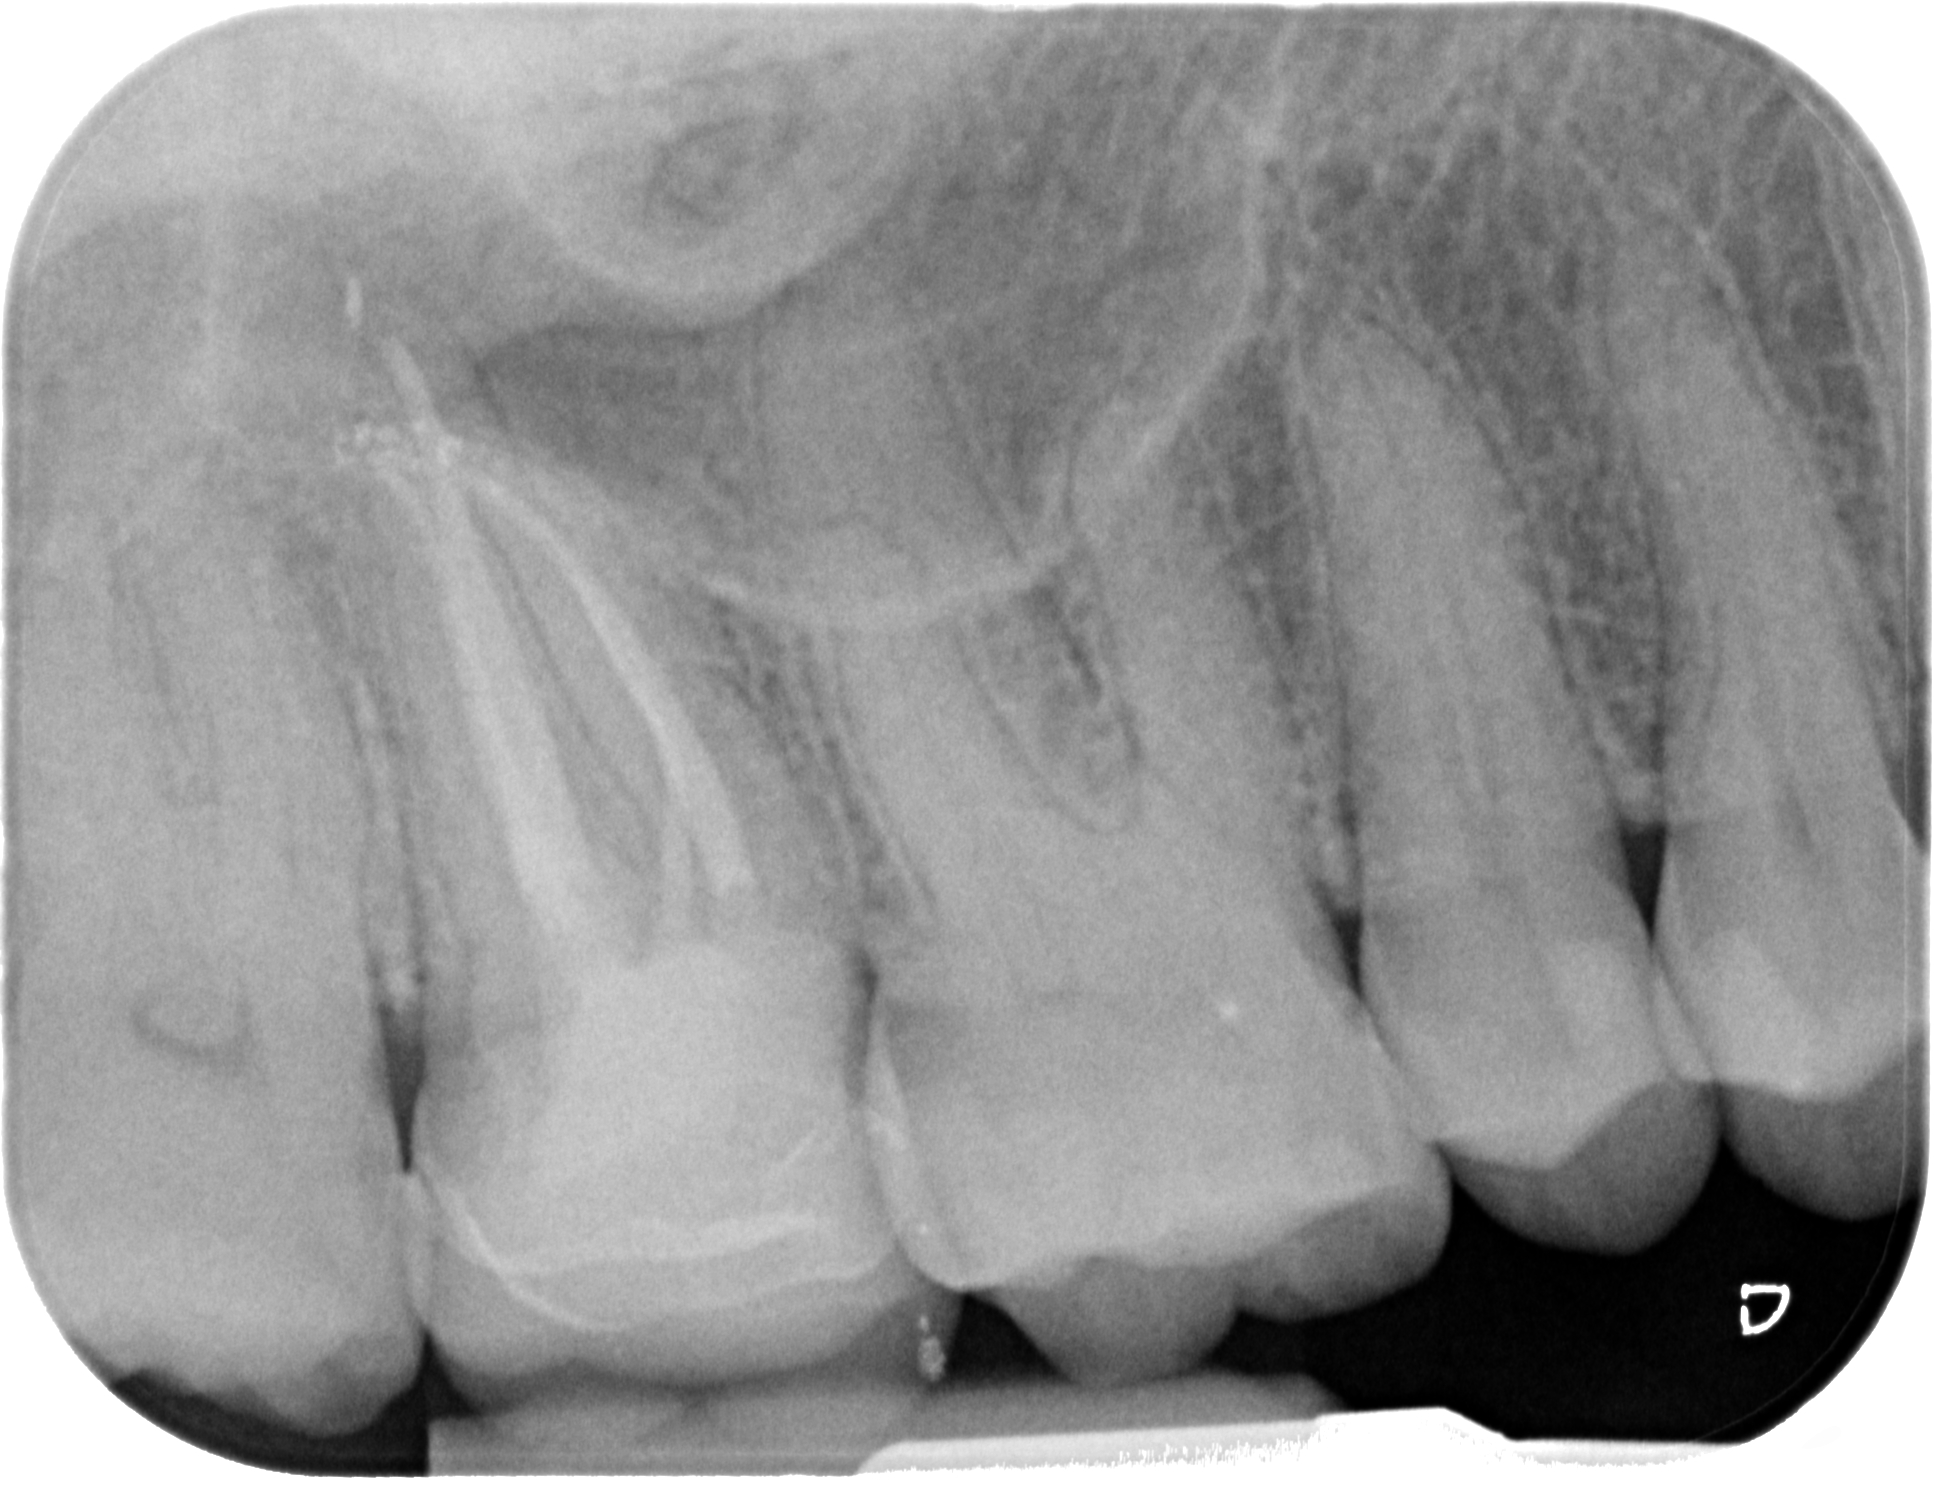

Fig. 5: One-year follow-up radiograph.